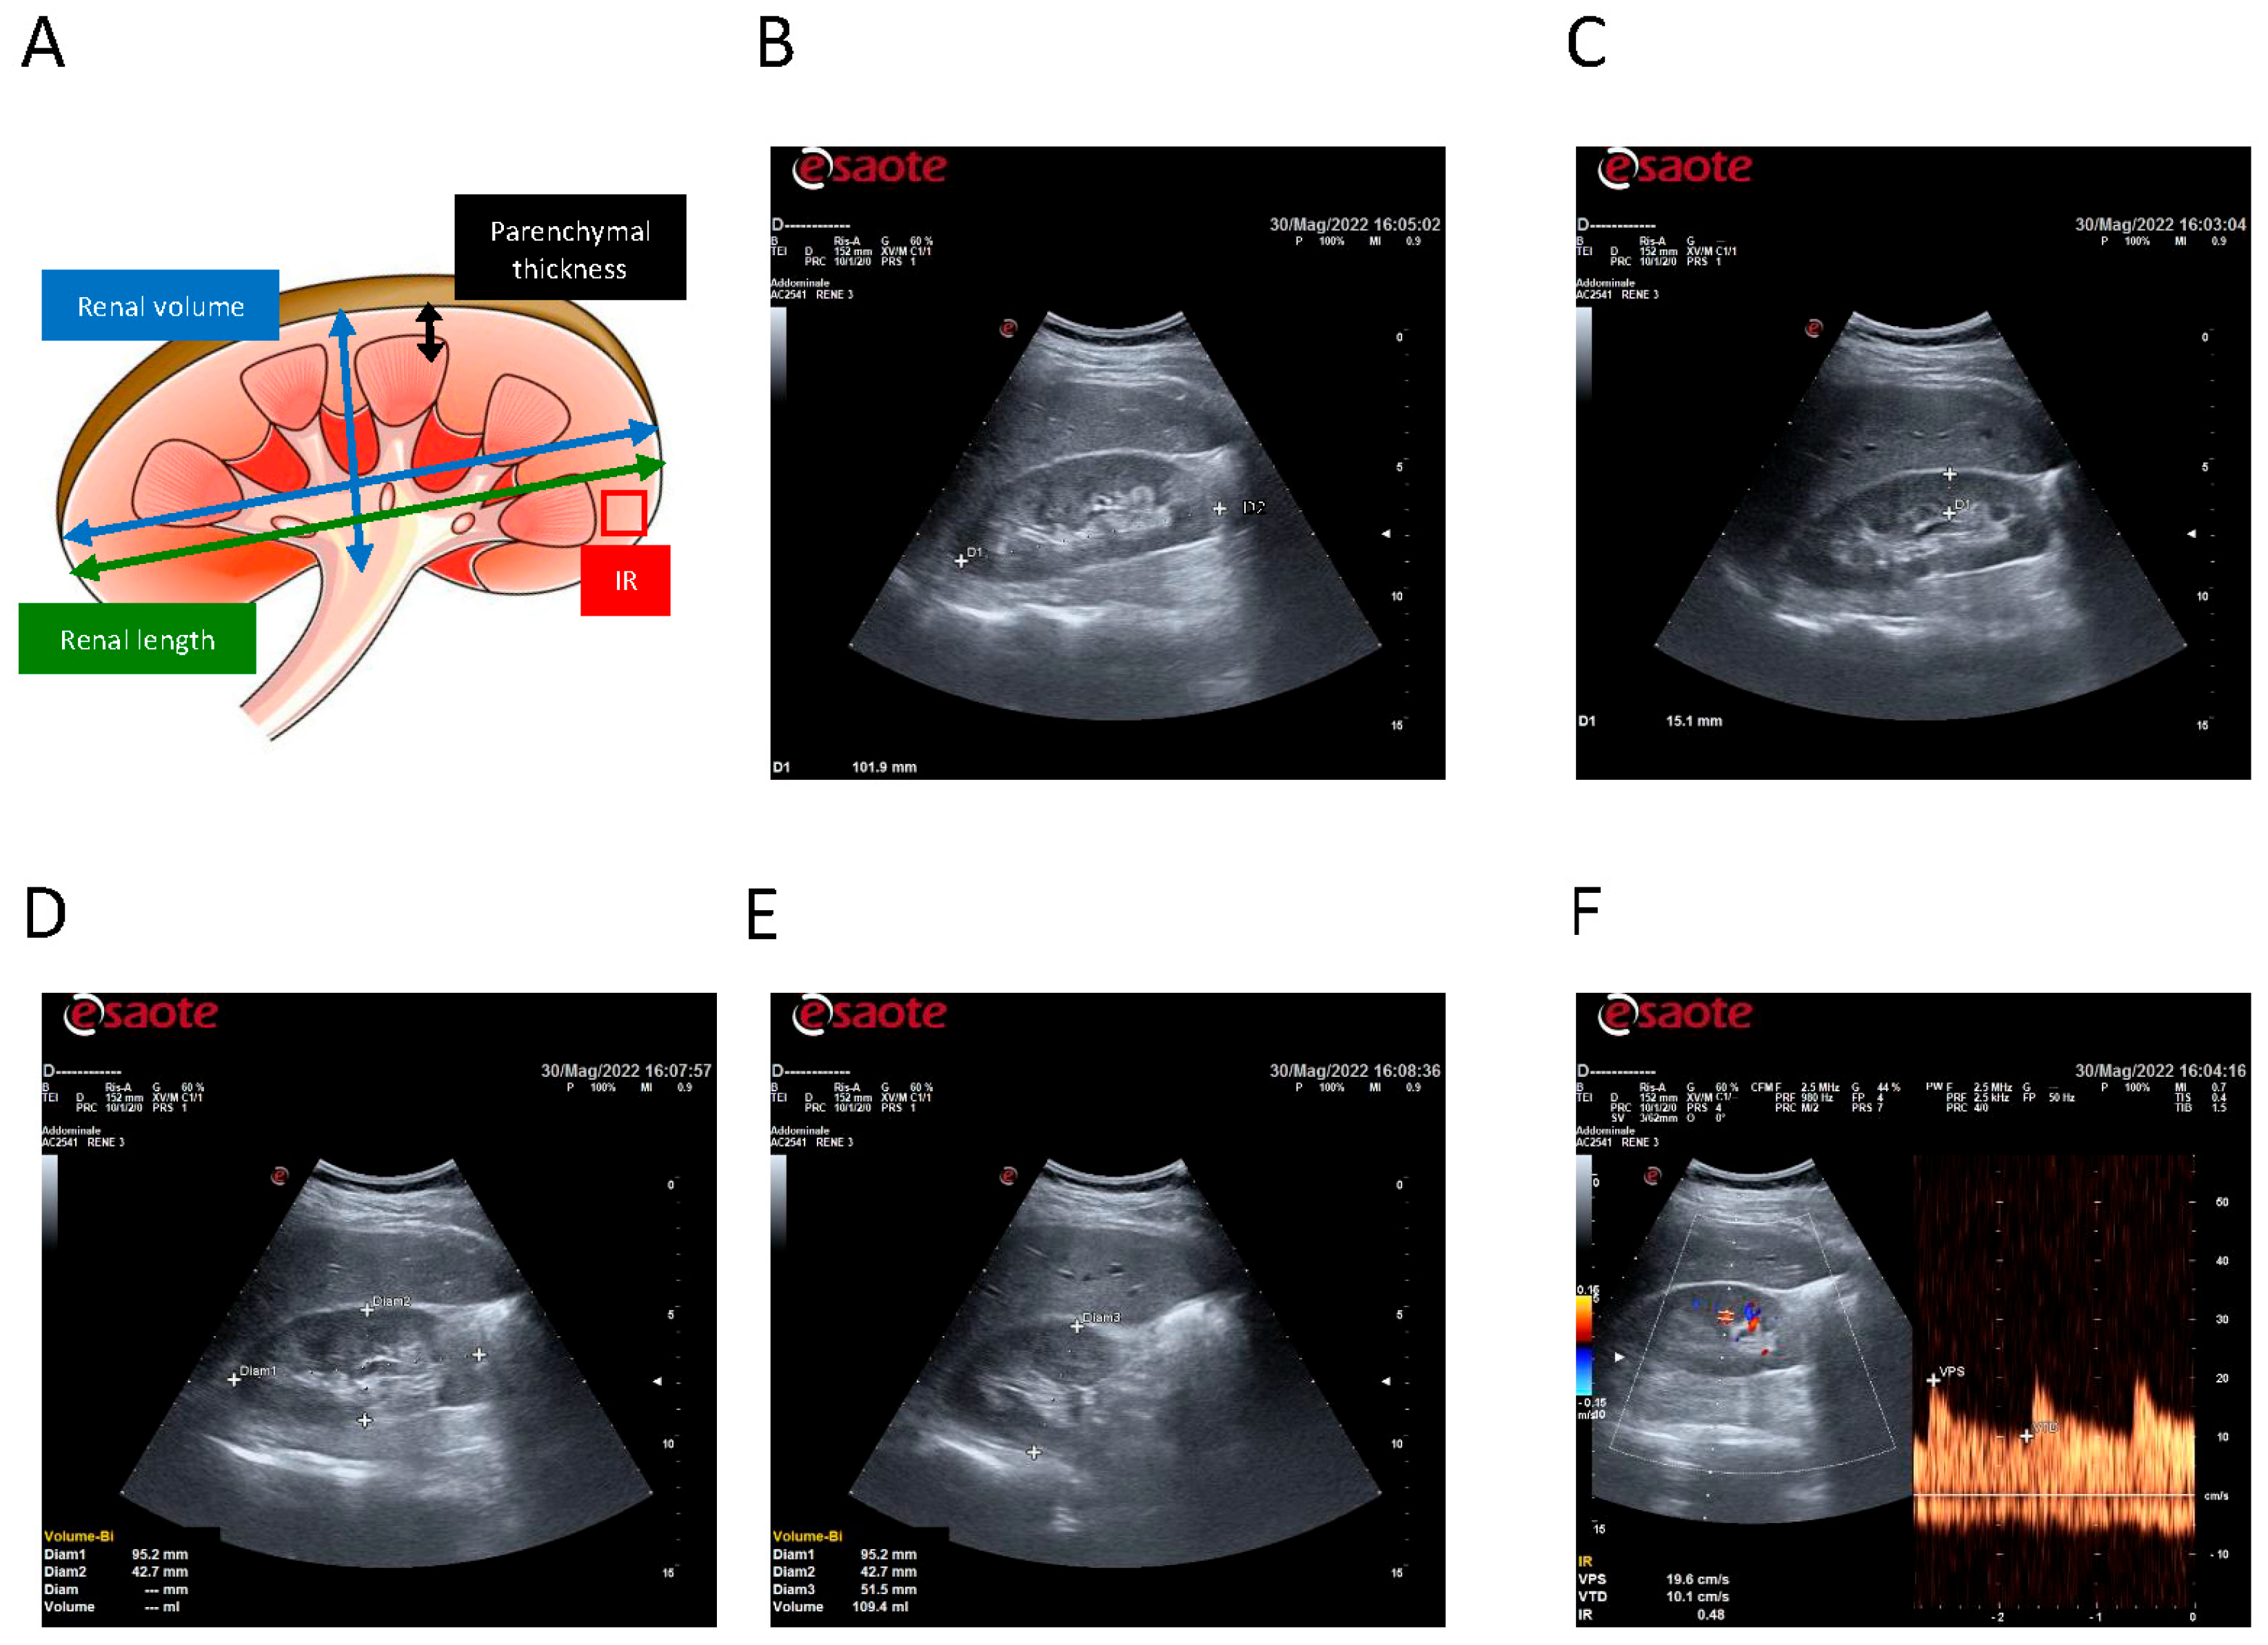

- Renal length: Defined as the maximal pole to pole distance and measured in a longitudinal view from upper to lower pole in both kidneys (mm).

- Parenchymal thickness: Measured as distance between the sinus fat and the renal capsule, assessed at the mesorenal level, avoiding cysts or structural anomalies (mm).

- Renal volume: Estimated using the ellipsoid formula (length × width × depth × 0.523) when feasible.

- Intrarenal resistive index (IR): Measured at interlobar arteries using pulsed-wave Doppler ultrasound. Three measurements per kidney were averaged.